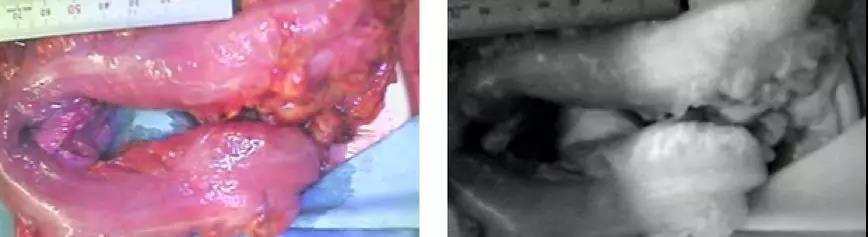

坂本教授:在日本,约80%的大肠癌手术用腹腔镜手术完成,腹腔镜操作结束后,从腹部小切口将切除的肠管运送到腹腔外。处理肠系膜血管,需要在切除肠管前进行。

用100cc的注射用水稀释2ml的ICG后静脉注射,使用PDE镜头观察ICG荧光。

坂本教授:投放ICG后,约50秒后就会流入肠管,发出荧光。这是需要注意ICG是怎么流入肠管的,都流到了什么位置。切除左侧结肠和直肠时我们观察切除肠管的口侧流域,切除右侧结肠时我们观察切除肠管的口侧和肛门侧领域。

发现有荧光不均匀的地方,以及染色缓慢的地方需要格外注意,鉴别了血流充分处后我们才能找到合适的切线。

据此,通过ICG荧光的帮助,我们有时可能临阵改变预先设定的切线,以达到更好的预后。